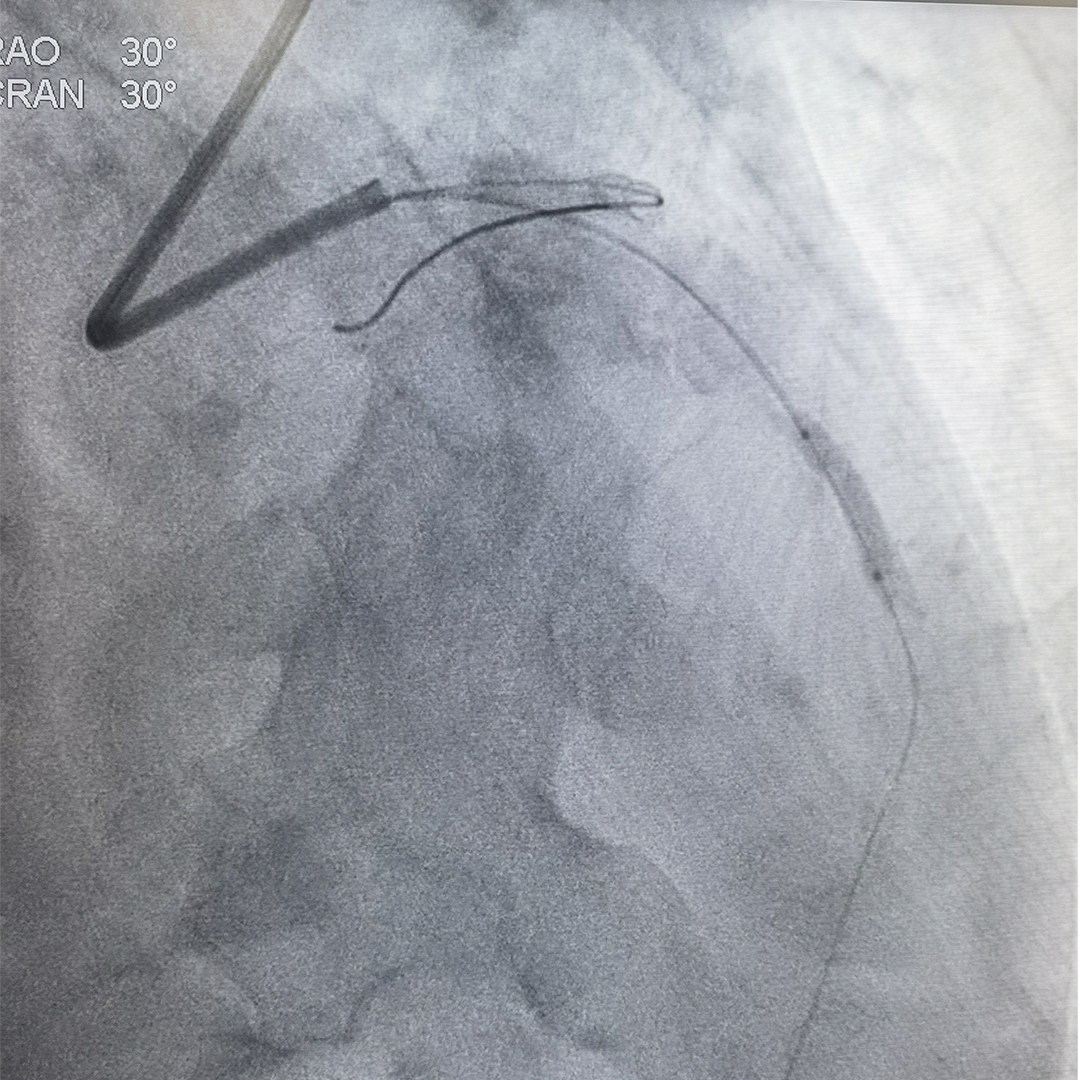

冠脉造影及IVUS检查提示前降支重度狭窄伴严重钙化